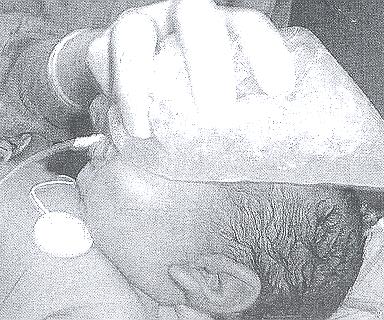

Figura

1a. Tracciato ECG in fase acuta, che mostra una tachicardia

parossistica sopraventricolare. Nel tracciato si evidenzia un’onda

P che segue il QRS, abbastanza distanziata da qualificare l’aritmia

come rientro attraverso una via accessoria.

1b. Tracciato ECG basale. Nel tracciato basale non si evidenzia

PR breve né una chiara onda delta: in epoca neonatale le vie

accessorie sono di solito “occulte”, non danno cioè

segno di sé nei tracciati ECG basali.

Si

tratta di una manovra di stimolazione vagale che viene usata come

approccio di prima linea nella TPSV nel paziente in buon compenso

clinico, prima di ricorrere all’adenosina. Si effettua premendo

sul volto del bambino per 15-20 secondi un guanto contenente

ghiaccio.